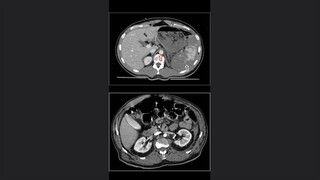

Radiología forense

Características históricas de la radiología forence